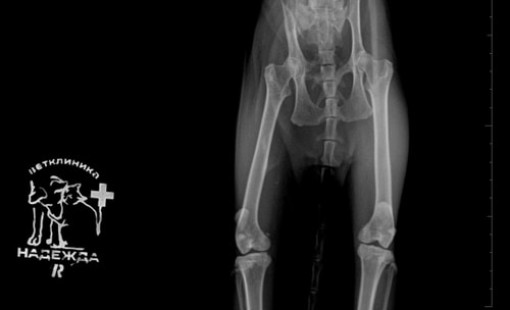

Случаи из практики

Ветеринарная клиника Надежда

За более чем 30-ти летнюю практику наши ветеринары сталкивались в различными случаями болезней и травм животных. Это дало нам огромный опыт в лечении и реабилитации. Мы беремся даже за самые сложные случаи! С любовью и заботой относимся к животным, стараемся сделать так, чтобы они испытывали минимум дискомфорта во время лечения и реабилитации.